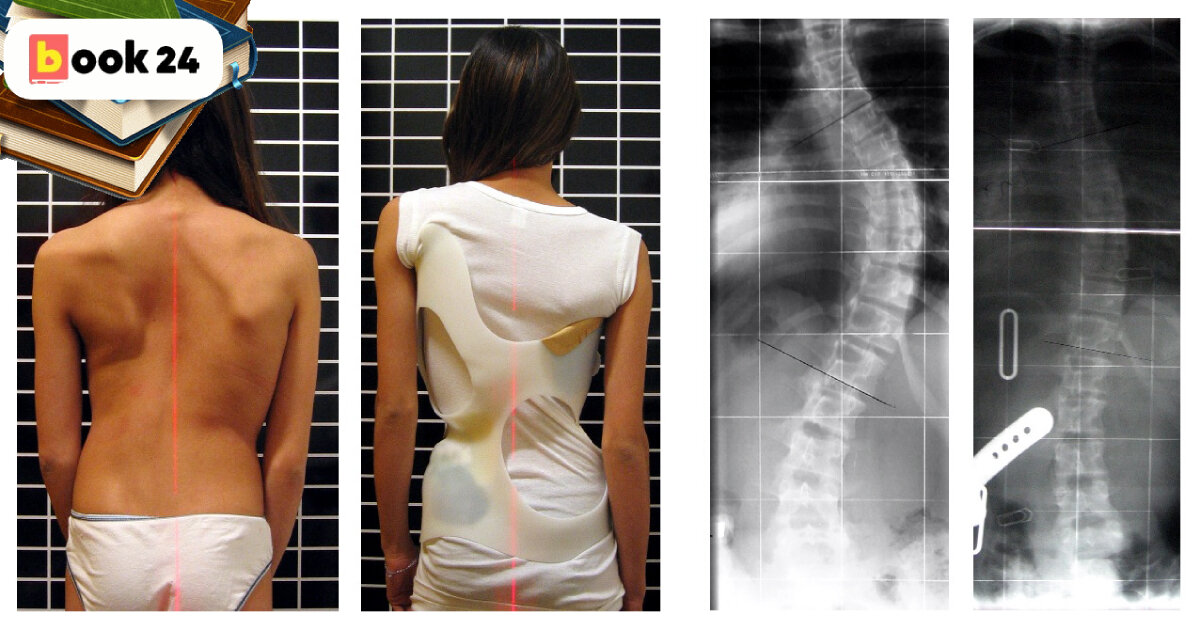

Из-за неровной осанки тело деформируется. Особенно ярко это видно в возрасте 12-13 лет, когда организм активно набирает в росте и развивается. Происходит неправильное размещение лопаток, неполное раскрытие грудной клетки, мышцы плеч и спины имеют сильную рельефность в одной части тела и полное отсутствие в другой. Некорректное расположение таза также влияет на длину и полноту ног, точнее на факт их различия между собой.